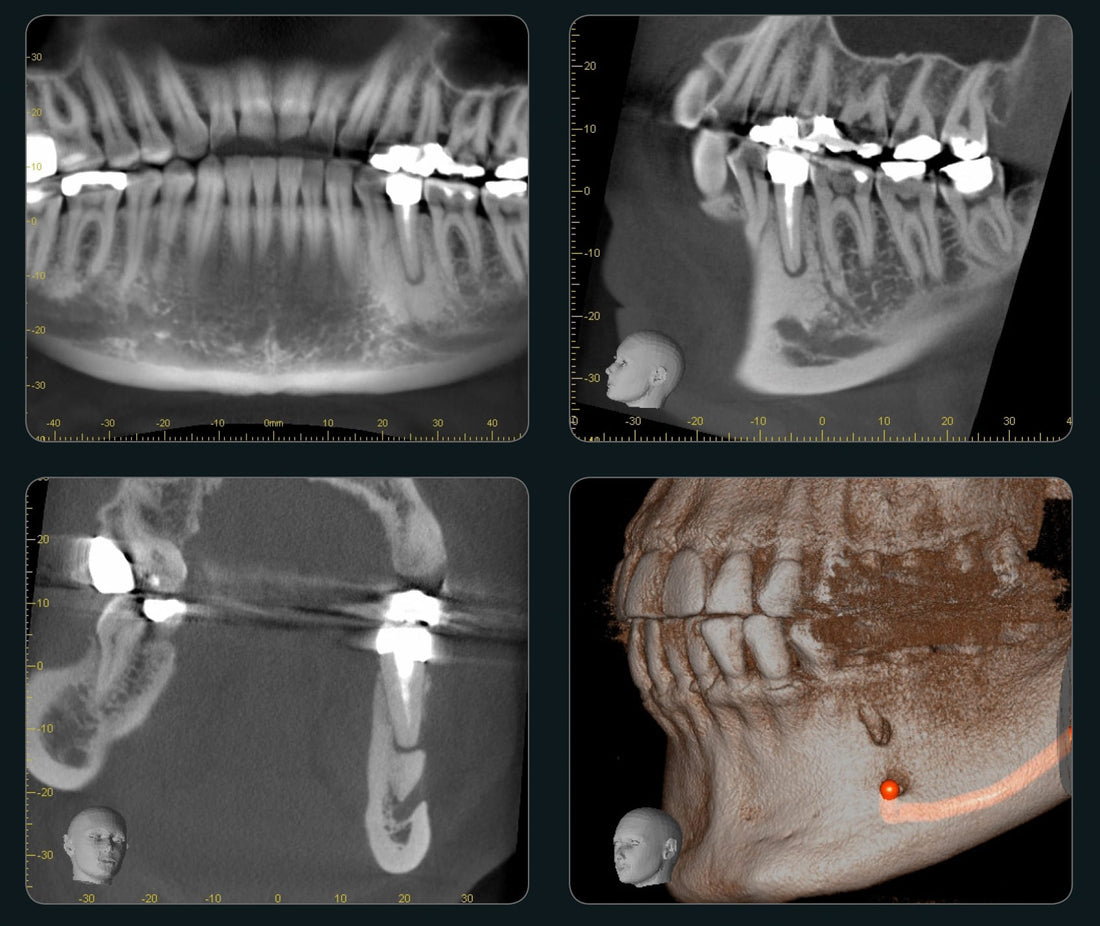

Cone Beam Computed Tomography (CBCT) is also known as C-arm CT, cone beam volume CT, flat panel CT, Digital Volume Tomography (DVT), or Digital Volume CT. Indonesia Cone-Beam Computed Tomography (CBCT) Systems Market is predicted to reach USD 15 million with a CAGR of 9% by 2030, according to industry analysts at Next Move Strategy Consulting.

Rising Dental Care Demand: The increasing awareness of oral health and advanced dental treatments in Indonesia is driving the demand for CBCT systems. These systems provide high-resolution 3D imaging for a range of dental procedures, including implants, orthodontics, and endodontics. As the dental care market expands, the adoption of CBCT technology is expected to rise.